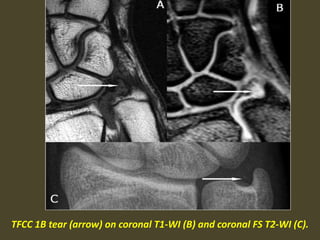

TFCC 1B tear (arrow) on coronal T1-WI (B) and coronal FS T2-WI (C).

Negative ulnar variance secondary to TFC tear.

Negative ulnar variance.